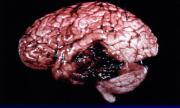

This diagram shows damage to brain tissue in a localized area due to bleeding. This is known as a what?

Contusion